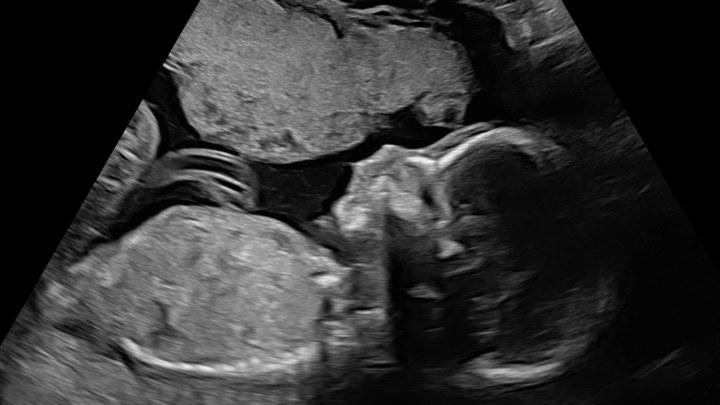

On April 9th, we received devastating news that our unborn baby was diagnosed with a Congenital Diaphragmatic Hernia, a rare and life threatening condition. CDH, is causing her organs to migrate into the chest cavity. Due to this, her heart is on the right side of her chest and her lungs have limited space to develop.